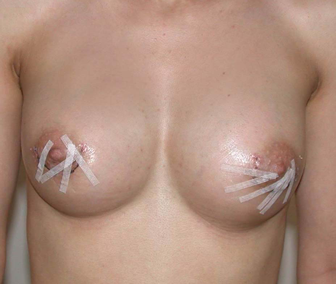

L’augmentation mammaire par pose d’implants est la seule alternative pour augmenter significativement et harmonieusement la taille des seins.

Les patientes de cet album ont des voies d’abord différentes, comme des tailles de prothèses ou de positionnement par rapport au muscle pectoral.